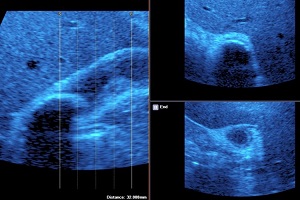

• Cholecystitis: Cholecystitis is Inflammation of gall bladder. Acute calculus cholecystitis results when calculus/calculi get impacted at neck of gall bladder or cystic duct.

• Finding: Sonography shows thickened oedmatous walls of gall bladder & impacted calculi. Sludge, pericholicystic fluid , localized abscess are additional findings. Sometimes gall bladder is so overdistended that impacted calculi may not be visualized.